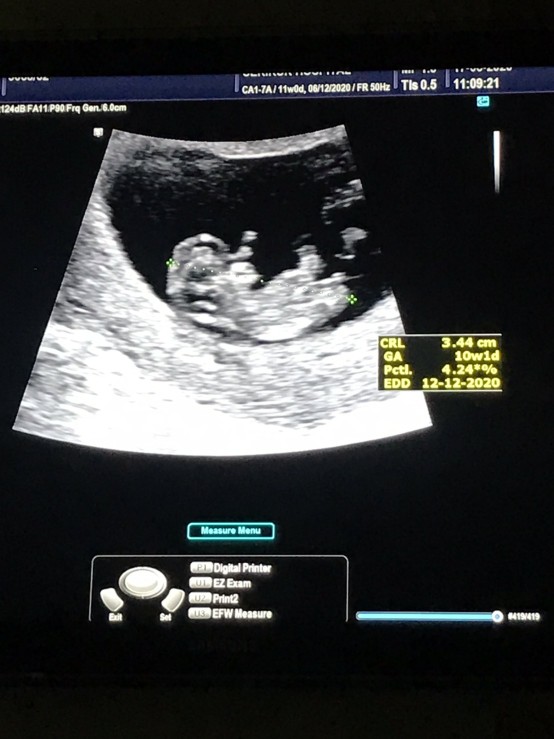

ขอดูใบซาวหน่อยจ้า เเล้วกำหนดคลอดวันที่เท่าไรกันค่ะ

12 ธันวาคมค่ะ

12 ธันวาคมจ้า